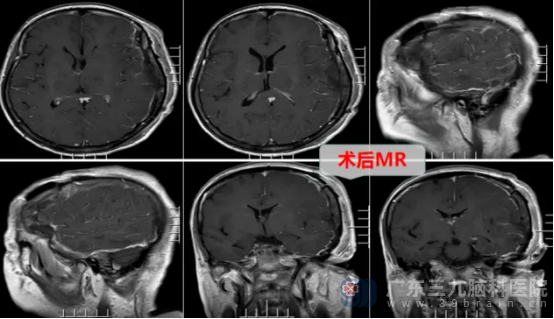

面对挑战,神经外十科团队迅速集结,深入研讨,审慎评估,制定周密手术方案。排除手术禁忌后,1月10日,一场与病魔的攻坚战打响。神经外十科学术带头人欧阳辉教授和副主任林德留带领医疗团队,凭借精湛技艺与丰富经验,如精细的工匠,在错综复杂的脑部组织间,小心分离肿瘤,全力守护正常组织,最终成功全切拳头大小的肿瘤。手术顺利完成。术后病理为脑膜皮细胞型脑膜瘤,CNS WHO1级,属于良性肿瘤。

术后,王女士恢复良好,神志清醒,能自动睁眼、遵嘱动作,很快就顺利出院了。